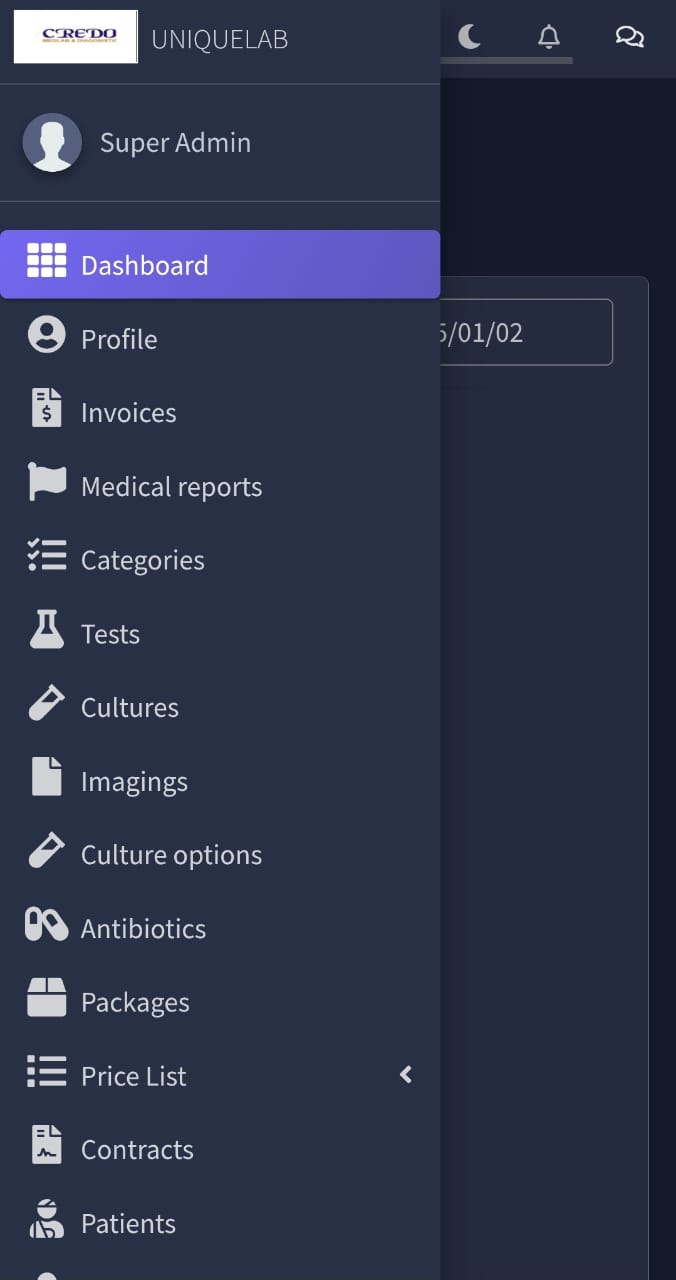

Perfect Responsive

Our Software & Website designs are fully Perfect for all device. You can use them on all device easily.

All in One

All you need to manage your business is embedded your choice software